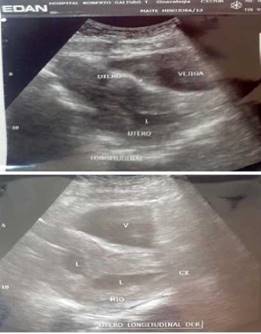

Figura 1 a y b: Ecografías Pélvicas donde se observan en ambas imágenes en un corte longitudinal derecho un útero en AVF. Aparentemente Didelfo bicorne asimétrico y/o subseptado aumentado de volumen y tamaño de aspecto heterogéneo donde se evidencia líquido anecoico en cavidad endometrial derecha probable colección obstruida sugestivo de Malformación Mulleriana tipo III- IV en estudio.